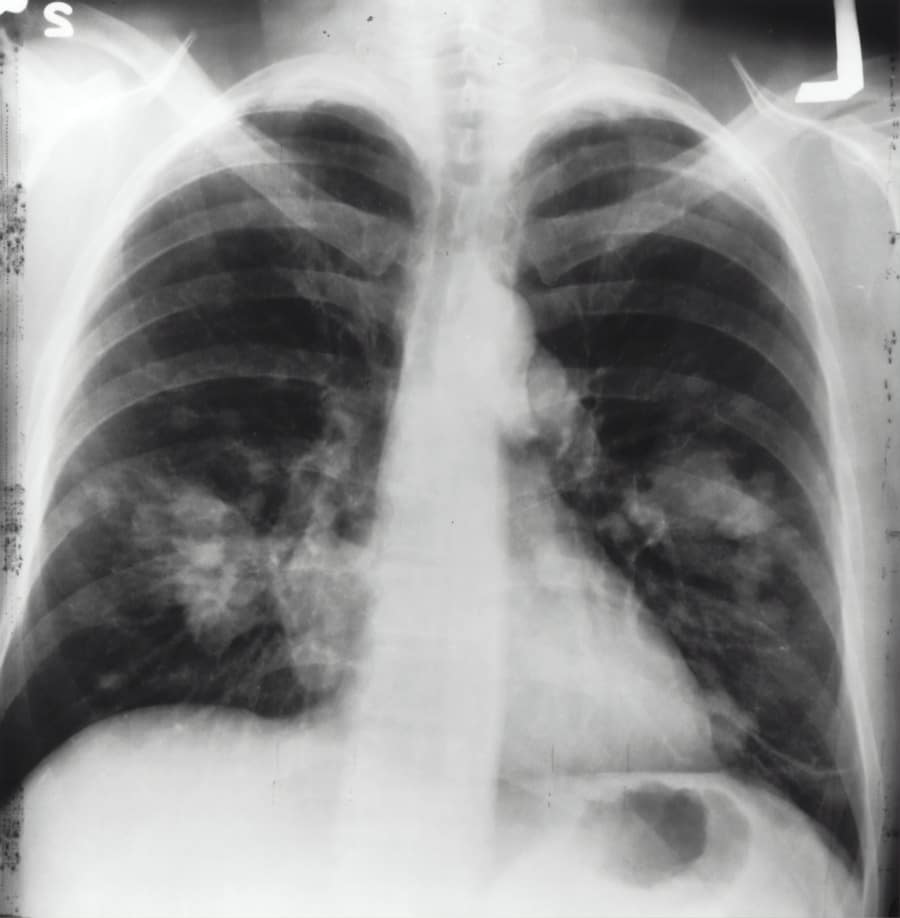

It is particularly effective in treating non-small cell lung cancer (NSCLC), which accounts for the majority of lung cancer cases. The drug has been approved for use in various stages of lung cancer, making it a versatile option in the oncologist’s arsenal. As I delved deeper into its mechanisms and applications, I began to appreciate how it represents a shift towards personalized medicine, where treatments are tailored to the individual characteristics of each patient’s tumor.

According to statistics, the five-year survival rate for lung cancer patients has hovered around 20%, largely due to late-stage diagnoses and the aggressive nature of the disease. However, advancements in treatment options, including immunotherapy drugs like Keytruda, have begun to shift these statistics in a more hopeful direction.

I find it encouraging to see that early detection and innovative therapies are gradually improving outcomes for many patients. The survival rates for lung cancer can vary significantly based on several factors, including the type of lung cancer, stage at diagnosis, and overall health of the patient. For instance, patients diagnosed with localized non-small cell lung cancer have a much higher five-year survival rate compared to those with metastatic disease.

This can lead to autoimmune reactions where the immune system mistakenly attacks healthy tissues. Conditions such as pneumonitis (inflammation of the lungs), colitis (inflammation of the colon), and endocrinopathies (disorders of hormone-producing glands) can occur. As I reflect on these potential complications, I realize how important it is for patients receiving Keytruda to maintain open communication with their healthcare team to monitor any unusual symptoms and manage side effects effectively.